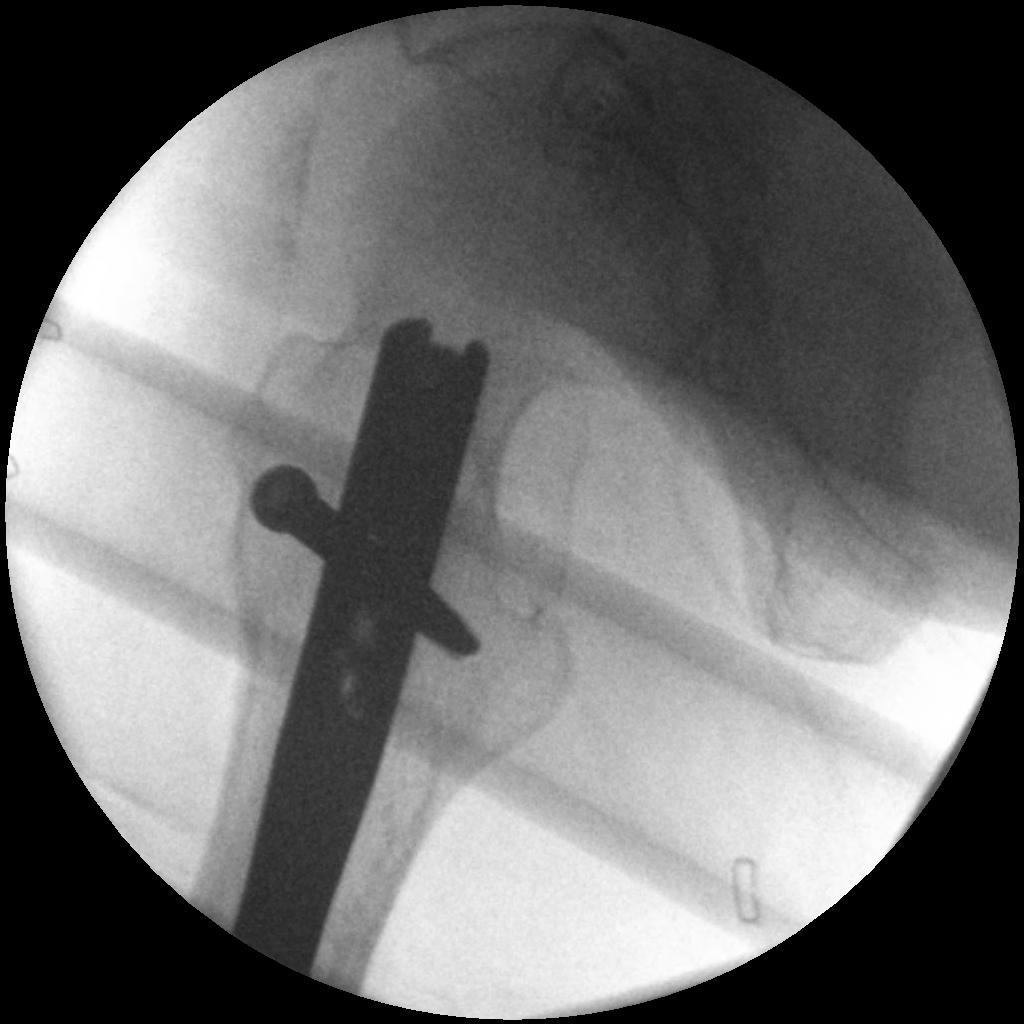

2. NOF (Neck of Femur) + Femoral shaft fracture

Must pay attention first to meticulous NOF ORIF

Options

1. Pin and Plate NOF / Retrograde Nail

2. Pin and Plate NOF / Plate femur

3. Reconstruction Nail

- difficult to anatomically reduce NOF

- increased incidence NOF non union

Difficult scenario

- antegrade IMN in place before diagnosis of NOF fracture

- if undisplaced, can place screws anterior to nail

- if displaced must remove nail

Results

Ostrum et al. CORR 2014

- 95 cases treated with proximal screws / sliding hip screws inserted first

- retrograde IMN second

- 98% union rate femoral neck

- 91% union rate femoral shaft